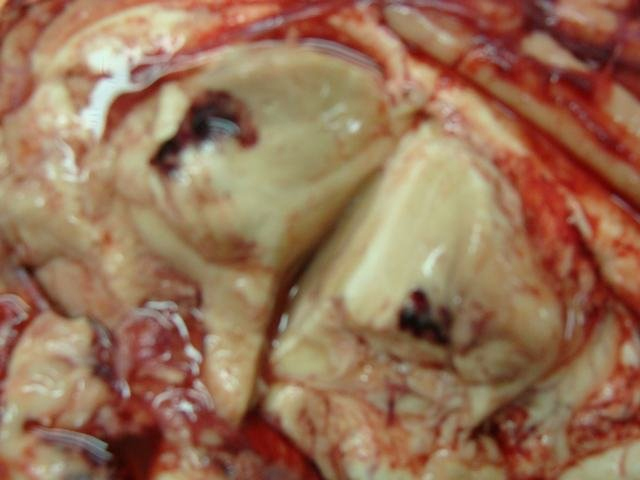

Content ยป Traumatic Haemorrhage Thalamus

traumatic haemorrhage in thalamus